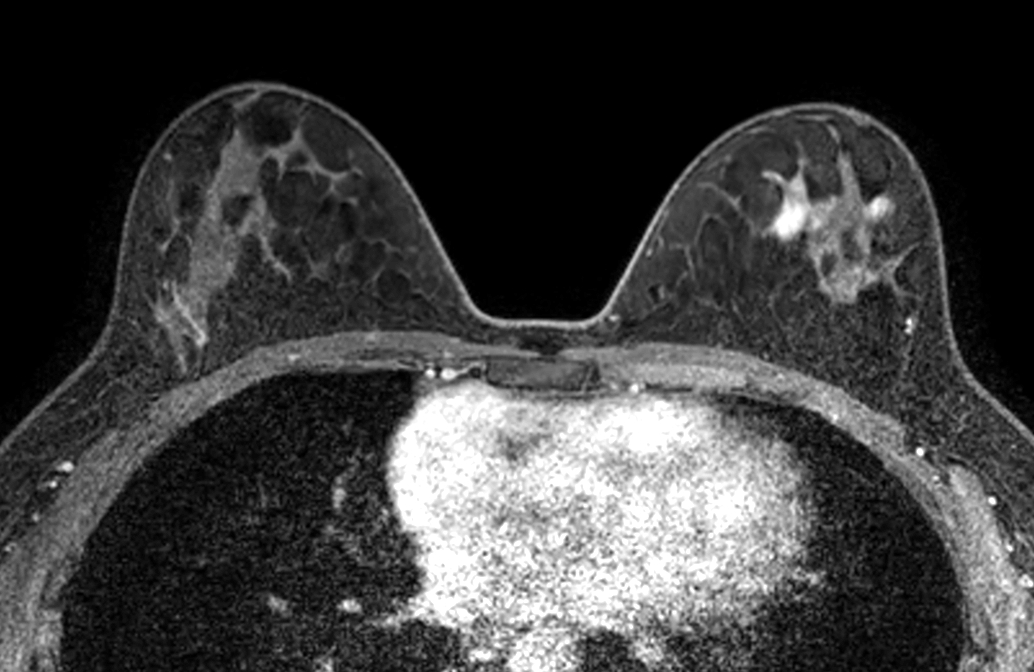

Axial mDIXON XD FFE (In Phase) - Dyn 4

Axial mDIXON XD FFE (Water only) - Dyn 4